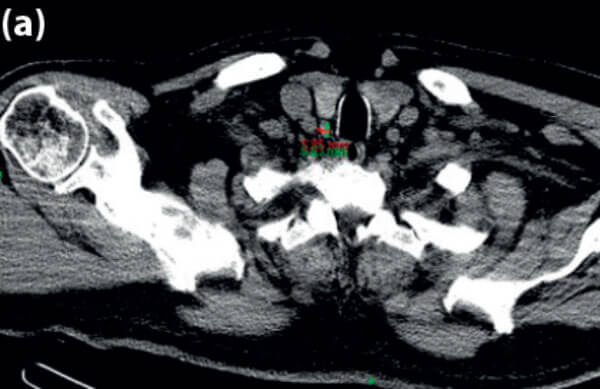

Using the PACS software, the corresponding CT images are viewed using multiplanar reconstruction (MPR). The PACS ruler is used to measure the following (see Figures 2-5).

- Size of the parathyroid gland in three dimensions.

- Distance from the cricoid to the parathyroid gland.

- Distance from posterior edge of thyroid to the parathyroid gland.

- Distance from the skin to the parathyroid gland.

(a).

(b).

Figure 2 (a) Axial CT scan showing PT gland measurements 5.85mm x 8.83mm; (b) arrow points to PT gland.